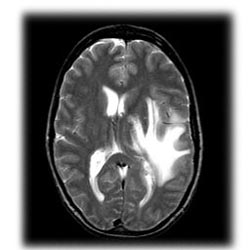

برای پژوهشگران مبحث اصلی در این زمینه این موضوع است که ریاضیدانان در حل مسائل پیچیده و بغرنج از چه بخشهایی از مغزشان استفاده میکنند، بهویژه اگر فرض کنیم انسانها هنگام حل مسائل ریاضی و استفاده از زبان از بخشهای مشترکی از مغزشان استفاده میکنند. پیرو همین موضوع، پژوهشگران در یک مطالعه جدید تمرکز خود را بر این مسئله گذاشته و در پی پاسخ این پرسش بوده که هنگام حل مسائل پیچیده ریاضی چه بخشهایی از مغز درگیر میشوند و در پی آن، چه توانمندیهای دیگری در انسان رشد میکند؟

در این پژوهش که توسط محققان دانشگاه پاریس در فرانسه انجام شده، مغز 15 ریاضیدان برتر و 15 فرد دانشگاهی که در رشتههای دیگر فعالاند زیر دستگاه اسکن fMRI * رفت و در این حین از آنها سوالاتی پرسیده شد که جواب آنها آری و خیر بود. برخی از این پرسشها در حوزه ریاضی و برخی دیگر زبان-محور بود. در این آزمایش، پژوهشگران دریافتند که در حالت عادی مسائل زبان-محور در همان بخشهای مربوط به زبان در مغز پردازش میشوند، اما وقتی همین پرسشها در کنار پرسشهایی که نیاز به پردازش بسیار پیشرفته داشت پرسیده میشد، ریاضیدانان از مناطق جداری، تمپورال جلویی و جلویی مغز خود برای حل آنها استفاده میکردند. در مورد افراد غیرریاضیدانان هیچ بخشی از مغز آنها درگیر نمیشد چراکه آنها قادر به درک مسائل ریاضی مطرحشده نبودند.